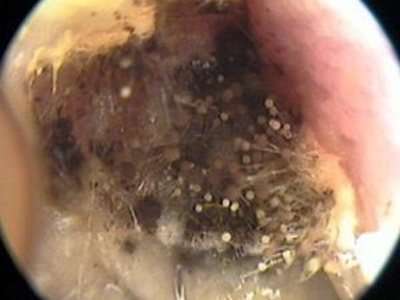

霉菌性外耳道炎耳朵里有深褐色片状附着物图

霉菌性外耳道炎患者的外耳道上附着有大量的干燥分泌物,呈圆形或花朵状,附着于耳朵上的茸毛上,外观形似蒲公英,并不断向内耳进行侵袭。